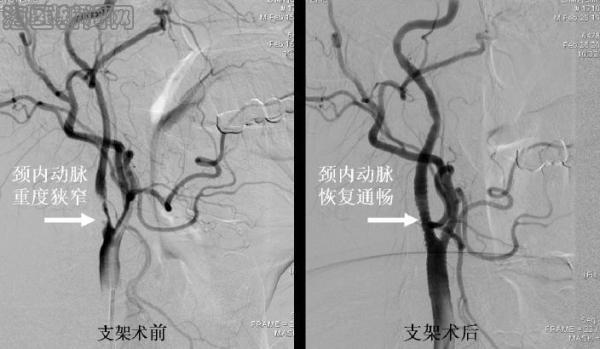

病例2 张某某,男,63岁,突发左侧肢体瘫痪入院,既往有吸烟和高血压病史,MRI检查发现右侧大面积脑梗死,全脑血管造影(DSA)发现右侧颈内动脉重度狭窄,脑供血明显不足,患者同意后在局麻下行颈动脉支架置入术,术后即刻造影显示颈动脉狭窄解除,血流恢复通畅,脑供血不足明显改善。患者术后瘫痪症状明显改善,第4天出院。术后随访1年8月,CT血管造影(CTA)显示支架通畅,患者独立行走。